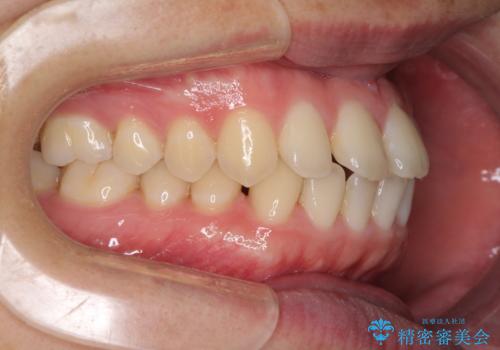

すきっ歯の改善 インビザライン矯正治療

- 上の前歯の隙間を気にして来院された患者様です。

インビザラインにより、上下の歯列を側方に拡大しつつ、前歯の隙間を閉じていくこととしました。

1日22時間の装着時間をしっかりと守ってくださったので、隙間がきれいに閉じ、口元の突出感も改善することができました。